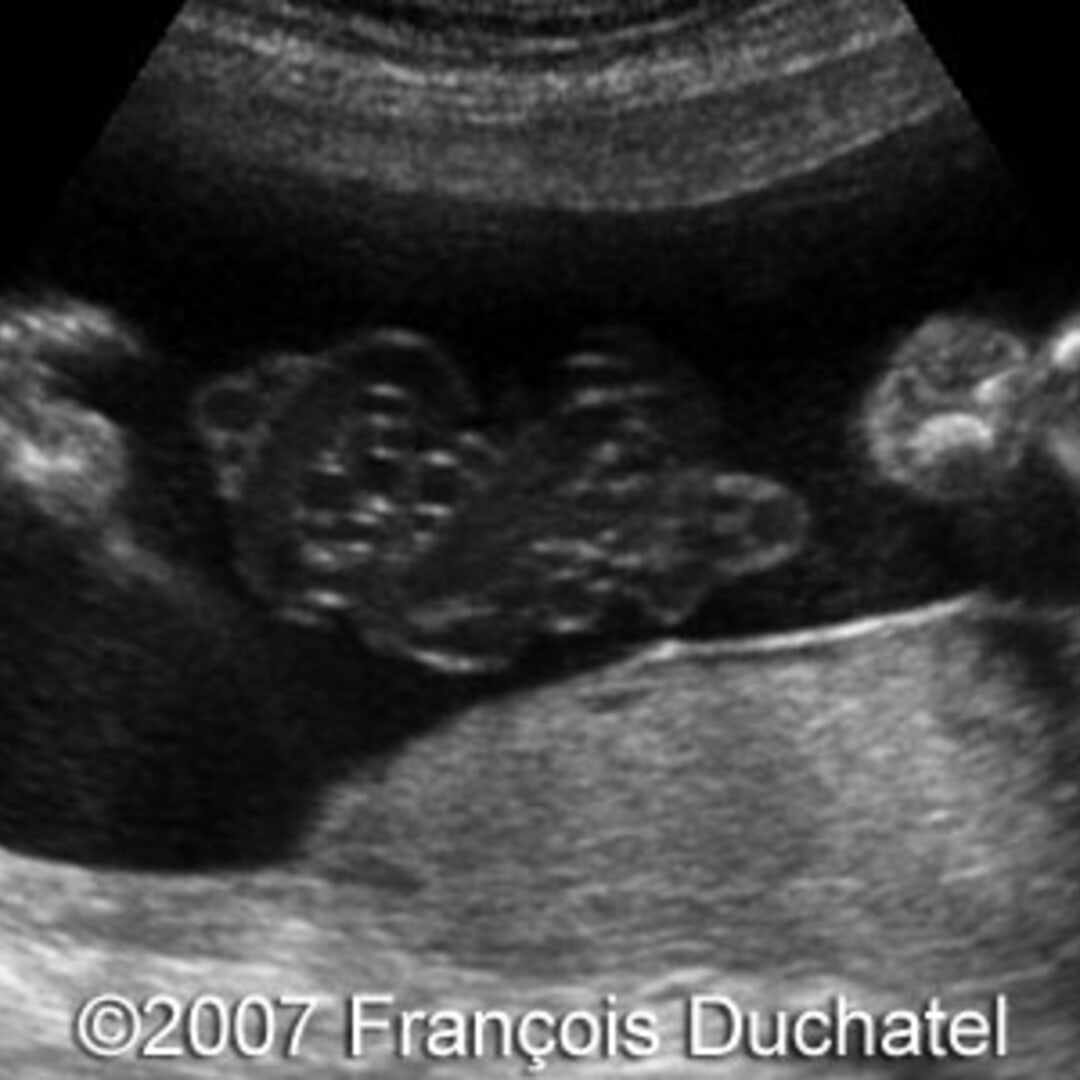

📃 Cord entanglement in monoamniotic twins What Is Cord Entanglement   cord entanglement is defined as an umbilical cord that encircles the fetal body, neck, or extremities [1].   umbilical cord entanglement is present in all monoamniotic twins when it is systematically evaluated by ultrasound and color doppler. Symptoms present in the baby shortly.  a nuchal cord is when the umbilical cord becomes wrapped around the fetus 's neck.. What Is Cord Entanglement.

📃 Cord entanglement in the first trimester What Is Cord Entanglement    umbilical cord entanglement is the most common pathological condition among umbilical cord abnormalities [1],.  umbilical cord entanglement in monoamniotic twins is a biologically plausible phenomenon that can be.  cord entanglement is defined as an umbilical cord that encircles the fetal body, neck, or extremities [1].   umbilical cord entanglement is present in all monoamniotic twins when it. What Is Cord Entanglement.